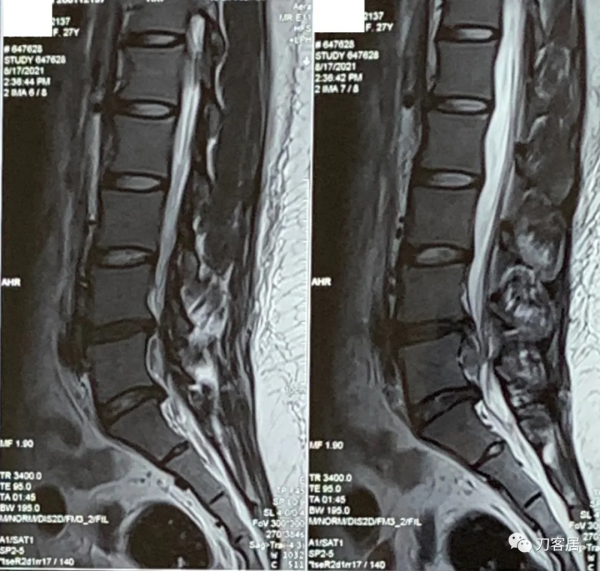

圖18. 20210920術後27天,腰椎MRI矢狀面,提示切口內訊號混亂,液性聚集。

圖19. 20210920術後27天,腰椎MRI橫截面,提示切口內訊號混亂,液性聚集。

圖20. 20211007術後44天,腰椎MRI提示腰椎切口內液性聚集,但切口周圍軟組織內混雜訊號好轉。

圖21. 20211007術後44天,腰椎MRI提示腰椎切口內液性聚集,但切口周圍軟組織內混雜訊號好轉。

圖22. 20211007術後44天,腰椎MRI提示腰椎切口內液性聚集,但切口周圍軟組織內混雜訊號好轉,但該T1相提示術野後部軟組織內仍有異常訊號影。

圖23. 20211007術後44天,腰椎MRI提示腰椎切口內液性聚集,但切口周圍軟組織內混雜訊號好轉,但該T1相提示術野後部軟組織內仍有異常訊號影。

圖24. 20211007術後44天,腰椎MRI提示腰椎切口內液性聚集,但切口周圍軟組織內混雜訊號好轉,但該T1相提示術野後部軟組織內仍有異常訊號影。

圖25. 20211007術後44天,腰椎MRI橫截面掃描提示腰椎切口內液性聚集,但切口周圍軟組織內混雜訊號好轉,但術野後部軟組織內仍有異常訊號影。

圖26. 20211007術後44天,腰椎MRI橫截面掃描提示腰椎切口內液性聚集,但切口周圍軟組織內混雜訊號好轉,但術野後部軟組織內仍有異常訊號影。

圖27. 20211007術後44天,腰椎MRI橫截面掃描提示腰椎切口內液性聚集,但切口周圍軟組織內混雜訊號好轉,但術野後部軟組織內仍有異常訊號影。